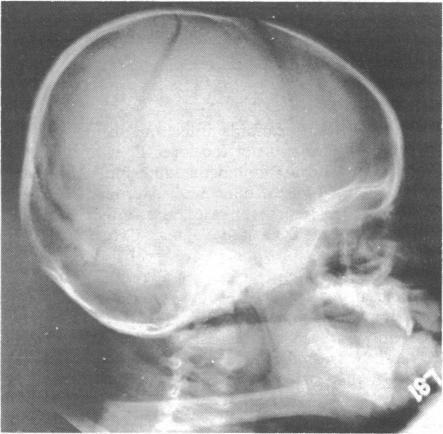

https://cdn.ncbi.nlm.nih.gov/pmc/blobs/1b0c/1587393/1cb307d515f2/brmedj01584-0048-a.jpg